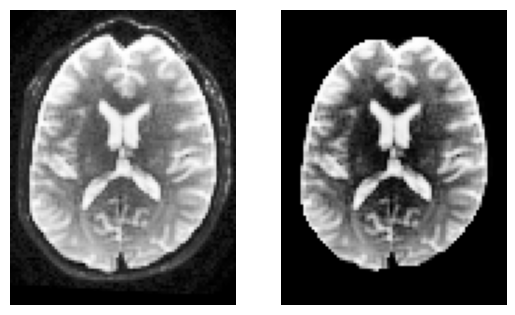

Minimal preprocessing#

To keep things simple, we’ll compute a brain mask using median_otsu.

This function is inspired from Mrtrix’s bet which has default values median_radius=3, numpass=2. However, from tests on multiple 1.5T and 3T data from GE, Philips, Siemens, the most robust choice is median_radius=4, numpass=4 (default)

sli = data.shape[2] // 2

plt.subplot(1, 2, 1).set_axis_off()

plt.imshow(histeq(data[:, :, sli,0].astype("float")).T, cmap="gray", origin="lower")

plt.subplot(1, 2, 2).set_axis_off()

plt.imshow(histeq(b0_masked[:, :, sli,0].astype("float")).T, cmap="gray", origin="lower")

<matplotlib.image.AxesImage at 0x7f22d40ed090>